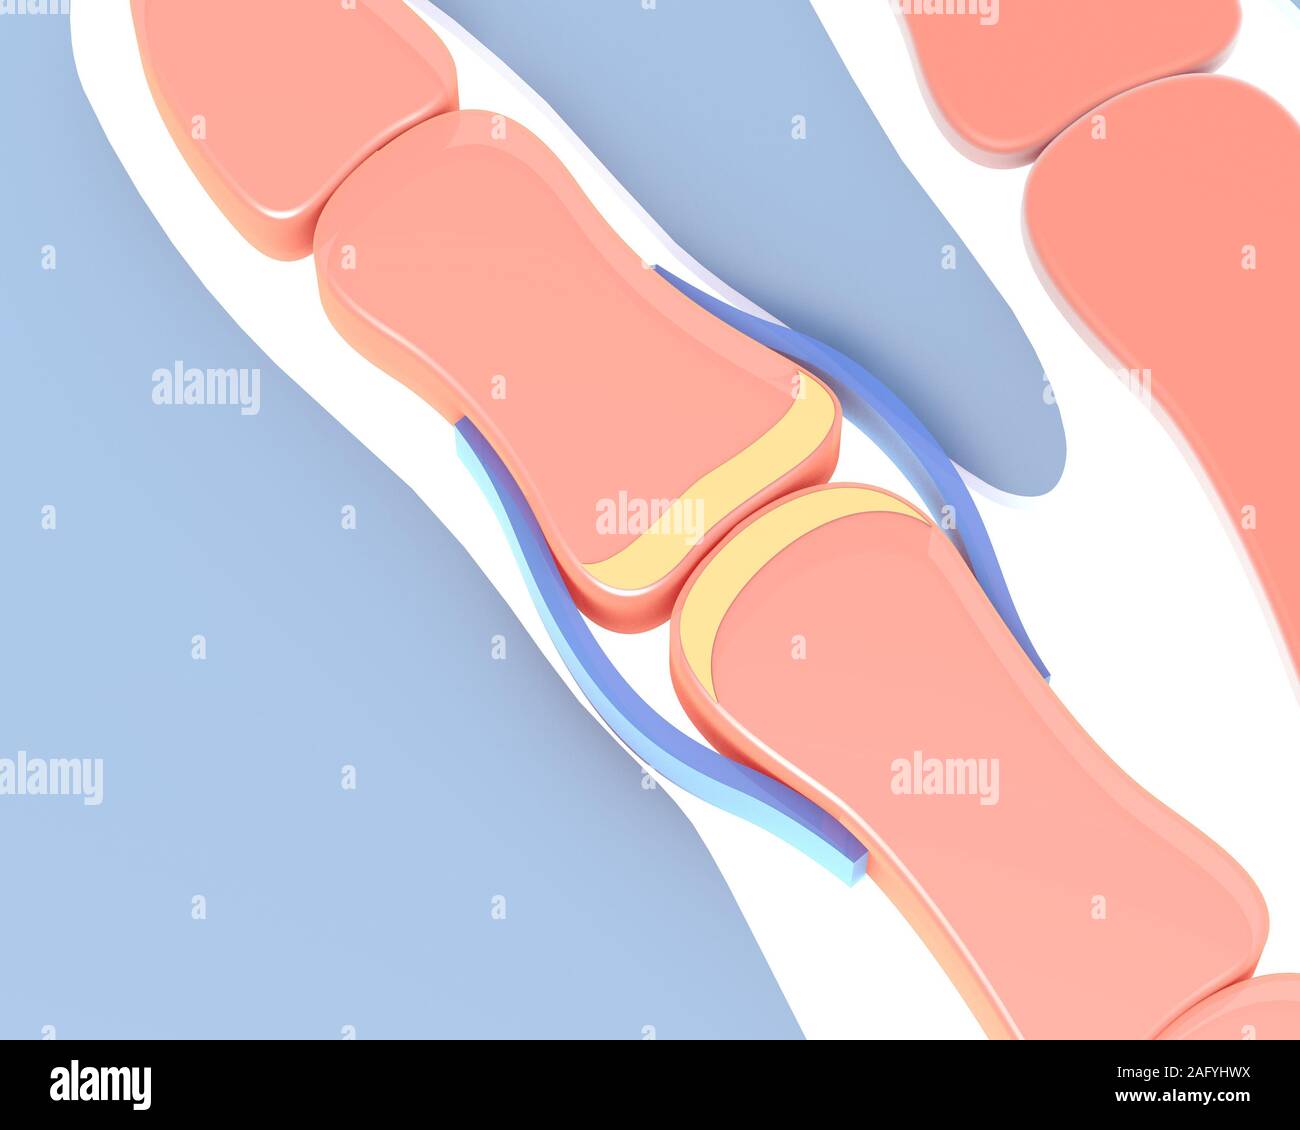

3d illustration of the synovial joint of the bone of a hand. Schematic and symbolic graphic representation. Stock Photohttps://www.alamy.com/image-license-details/?v=1https://www.alamy.com/3d-illustration-of-the-synovial-joint-of-the-bone-of-a-hand-schematic-and-symbolic-graphic-representation-image336823581.html

3d illustration of the synovial joint of the bone of a hand. Schematic and symbolic graphic representation. Stock Photohttps://www.alamy.com/image-license-details/?v=1https://www.alamy.com/3d-illustration-of-the-synovial-joint-of-the-bone-of-a-hand-schematic-and-symbolic-graphic-representation-image336823581.htmlRF2AFYHWH–3d illustration of the synovial joint of the bone of a hand. Schematic and symbolic graphic representation.

3d illustration of the synovial joint of the bone of a hand. Schematic and symbolic graphic representation. Stock Photohttps://www.alamy.com/image-license-details/?v=1https://www.alamy.com/3d-illustration-of-the-synovial-joint-of-the-bone-of-a-hand-schematic-and-symbolic-graphic-representation-image336823590.html

3d illustration of the synovial joint of the bone of a hand. Schematic and symbolic graphic representation. Stock Photohttps://www.alamy.com/image-license-details/?v=1https://www.alamy.com/3d-illustration-of-the-synovial-joint-of-the-bone-of-a-hand-schematic-and-symbolic-graphic-representation-image336823590.htmlRF2AFYHWX–3d illustration of the synovial joint of the bone of a hand. Schematic and symbolic graphic representation.